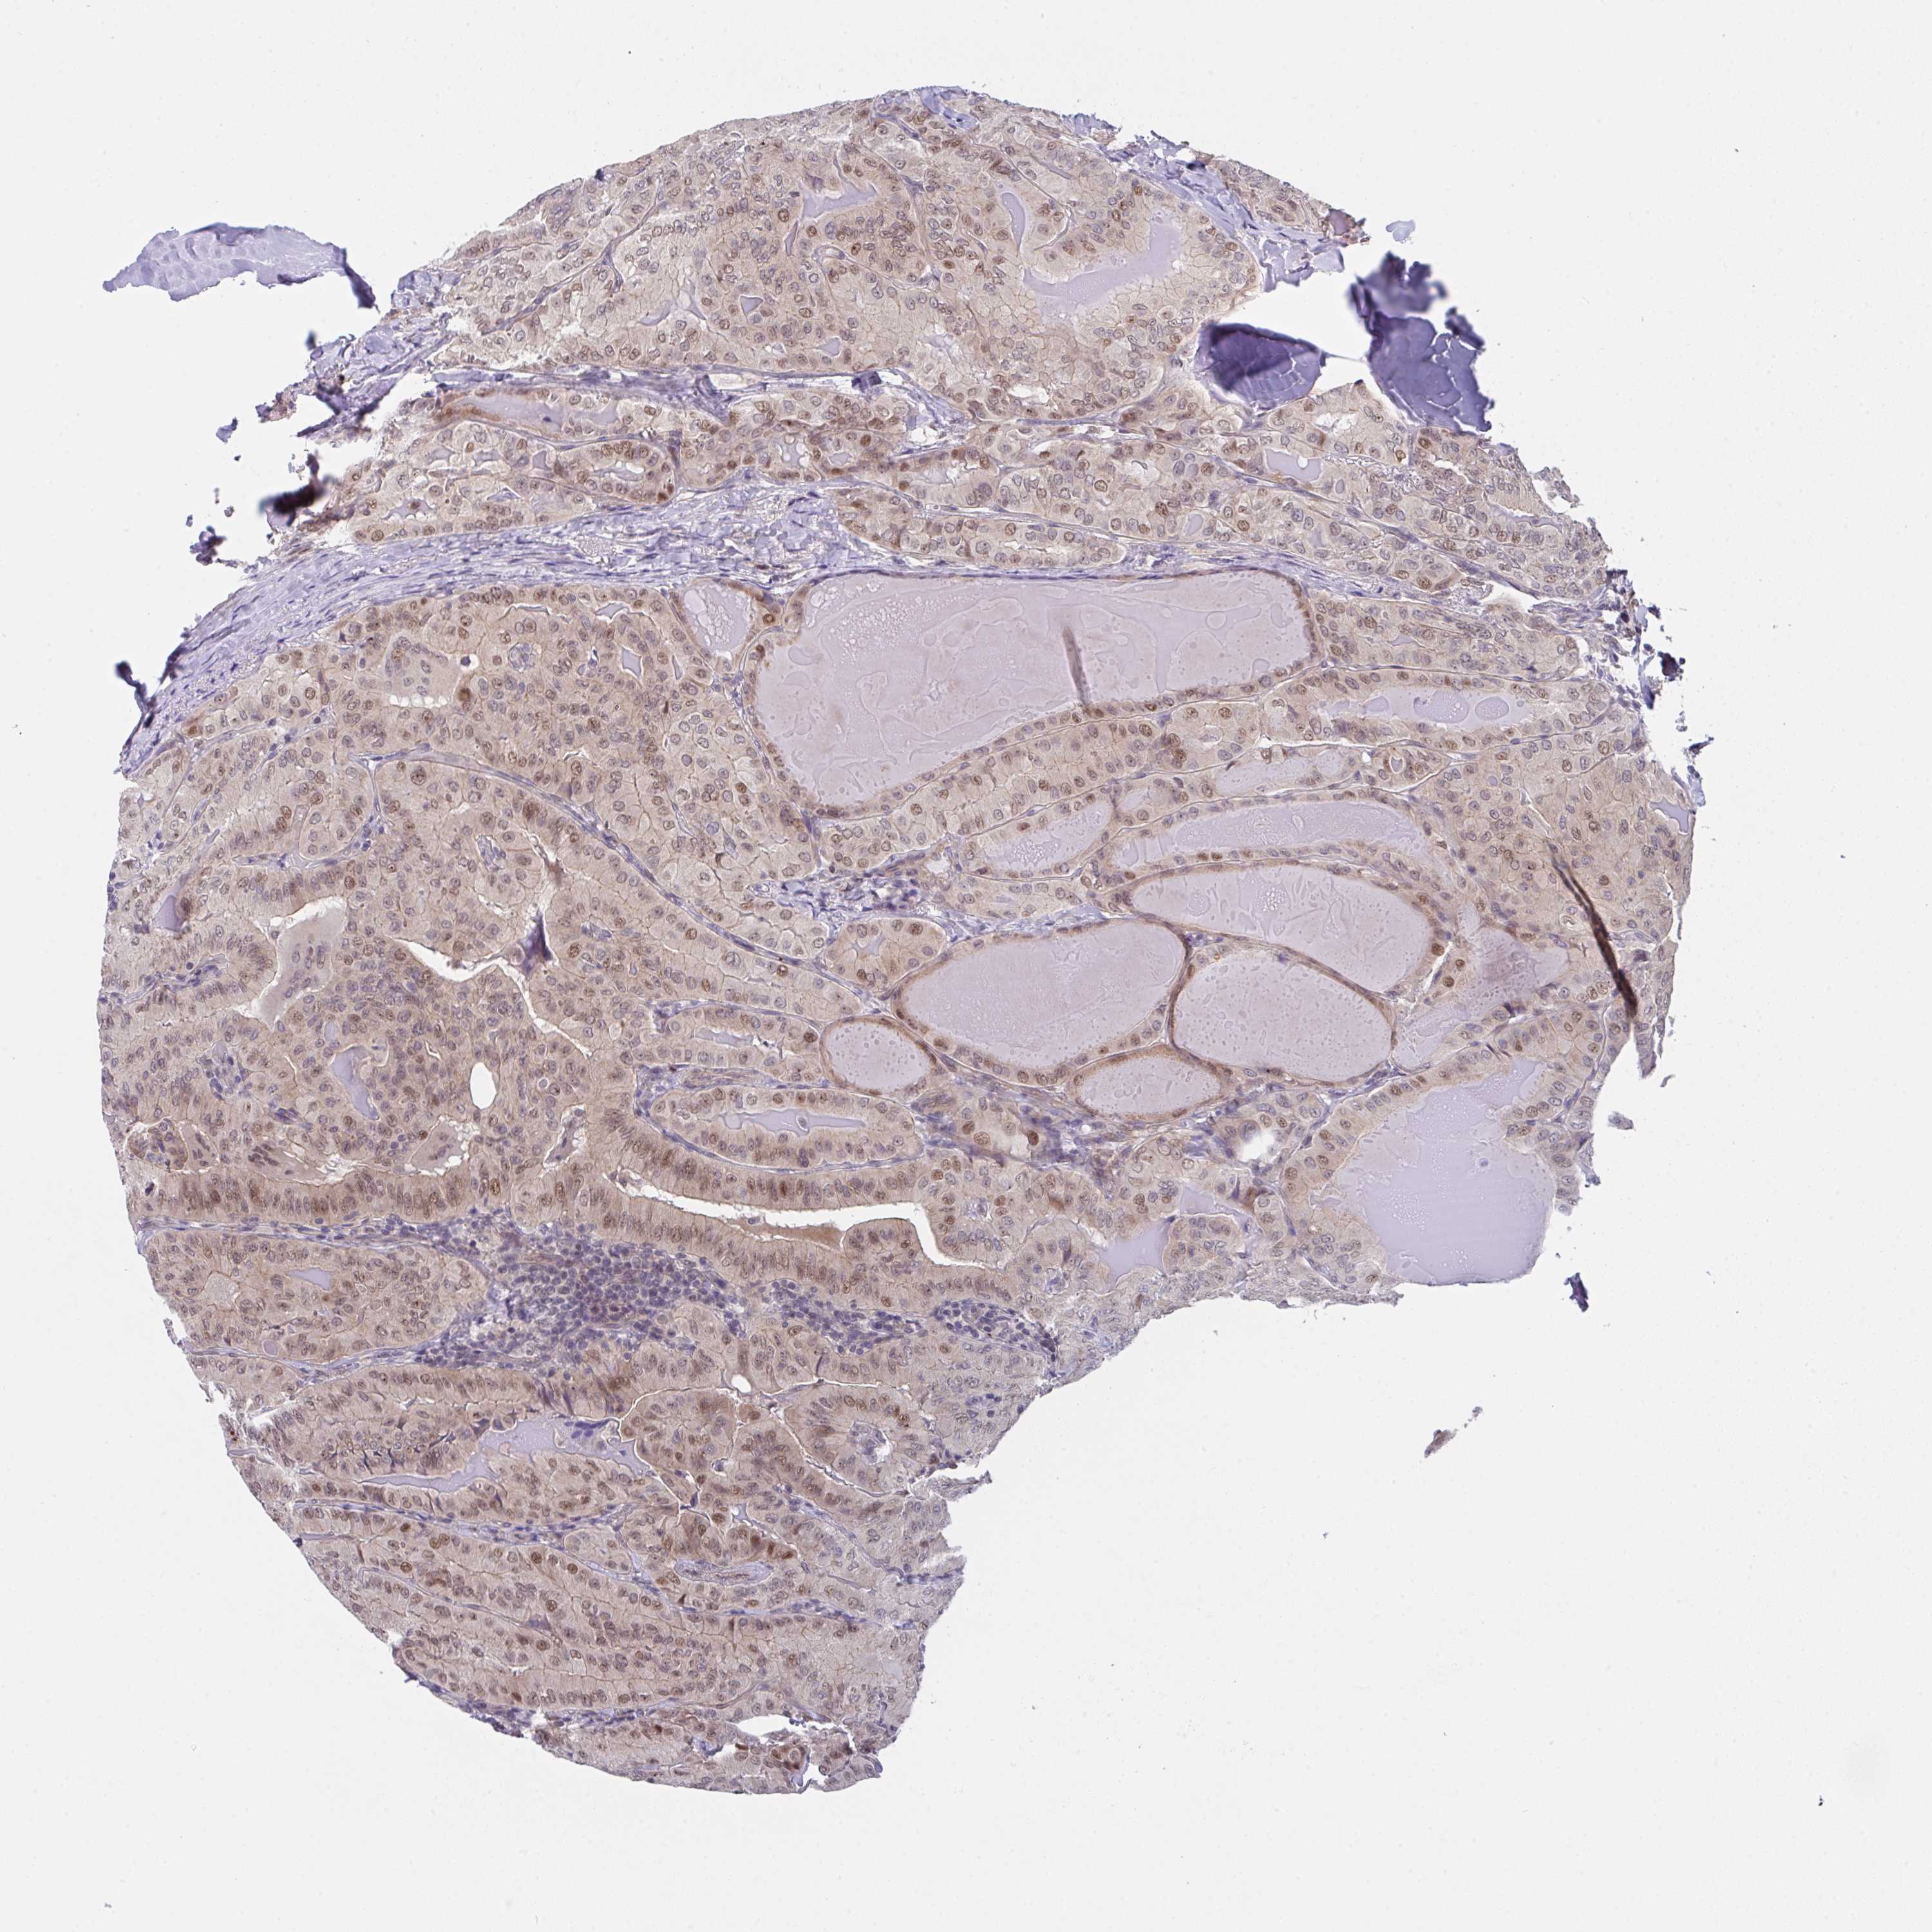

THYROID CANCER - Protein expressioni

A mouse-over function shows sample information and annotation data. Click on an image to view it in a full screen mode. Samples can be filtered based on level of antibody staining by selecting one or several of the following categories: high, medium, low and not detected. The assay and annotation is described here.

Note that samples used for immunohistochemistry by the Human Protein Atlas do not correspond to samples in the TCGA dataset.

Antibody stainingi

Antibody staining in the annotated cell types in the current human tissue is reported as not detected, low, medium, or high, based on conventional immunohistochemistry profiling in selected tissues. This score is based on the combination of the staining intensity and fraction of stained cells.

Each image is clickable and will lead to virtual microscopy that enables deeper exploration of all samples and also displays staining intensity scores, fraction scores and subcellular localization as well as patient and tissue information for each sample.

Antibody HPA057281

Papillary adenocarcinoma, NOS

Follicular adenoma carcinoma, NOS